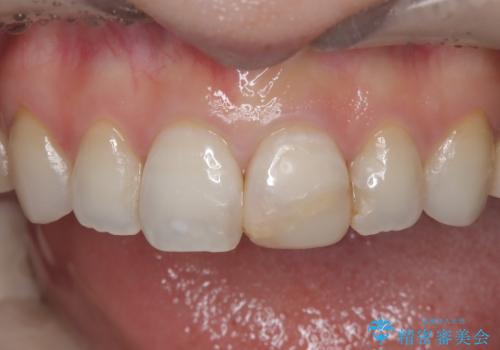

- 「前歯の色が気になる」を主訴に来院された患者さんです。以前他院にて、前歯2本をCR(プラスチック)で治療されていたところが劣化し変色していました。歯の長さも左右で異なっている状態でした。大部分がCR(プラスチック)修復されていたので、オールセラミッククラウンで治療を行いました。

古いCR(プラスチック)とその下の虫歯を除去した後に新しい土台を立てています。適合が良い被せ物を作るために拡大鏡を使用しながら歯を削り、変形のほとんどないシリコンという材料で型取りを行っています。